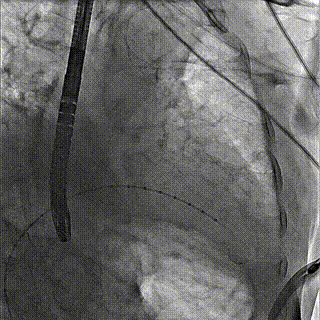

团队前期经过多次讨论,制定了周密的手术策略和预案。由于患者已是近九旬的超高龄老人,传统外科开胸手术风险极高,纯介入经血管三尖瓣替换能够明显减少创伤。术中陈茂及冯沅教授结合体表定位在造影指示下精准穿刺右侧颈静脉并预置两把血管缝合器。成功建立经皮血管入路后在食道超声和DSA的引导下顺利完成人工瓣膜植入,术后超声和造影显示人工三尖瓣同轴性良好,瓣架固定牢靠,无反流和瓣周漏,平均跨瓣压差降为1mmHg。术毕收紧预置的血管缝合器缝线完成止血,缝合效果满意,在手术室即刻拔除气管插管。

术后DSA造影